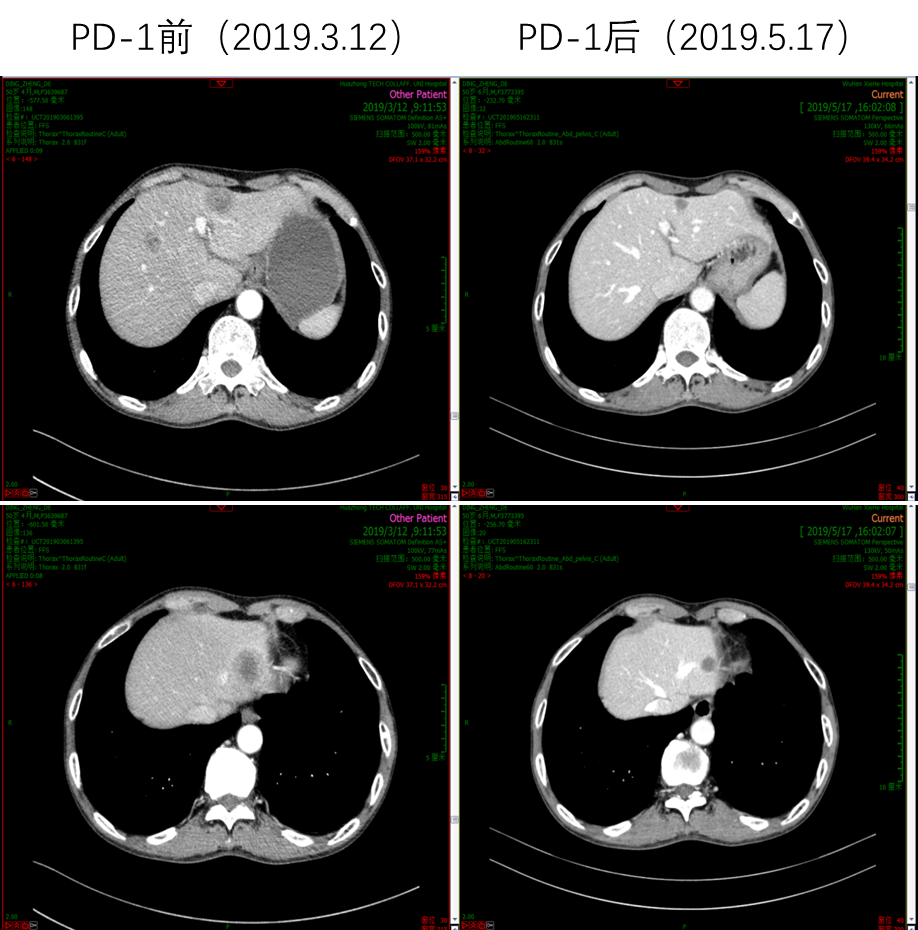

因患者PS评分差,故推荐单药PD-1单抗治疗,患者考虑后选择信迪利单抗。2019年3月20日开始使用信迪利单抗治疗1次,当日出现发热39.3℃,予以退热栓退热治疗后好转。4天后,患者PS评分明显好转,下床活动自如,食欲增强,PS评分由3分改善到1分。2019年4月11日和2019年5月1日分别再使用信迪利单抗治疗各1次。2019年5月17日复查腹部CT,肝脏病灶较前明显缩小,肝门淋巴结较前明显缩小;复查胸部CT,肺部病灶也较前明显缩小。总体疗效评价为PR。多次治疗中外周血EBV-DNA拷贝数检测结果显示,信迪利单抗治疗后EBV-DNA明显降低。

image013.png

图4 信迪利单抗治疗前后肝脏病灶明显缩小

image017.png

图5  信迪利单抗治疗前后肝门淋巴结明显缩小